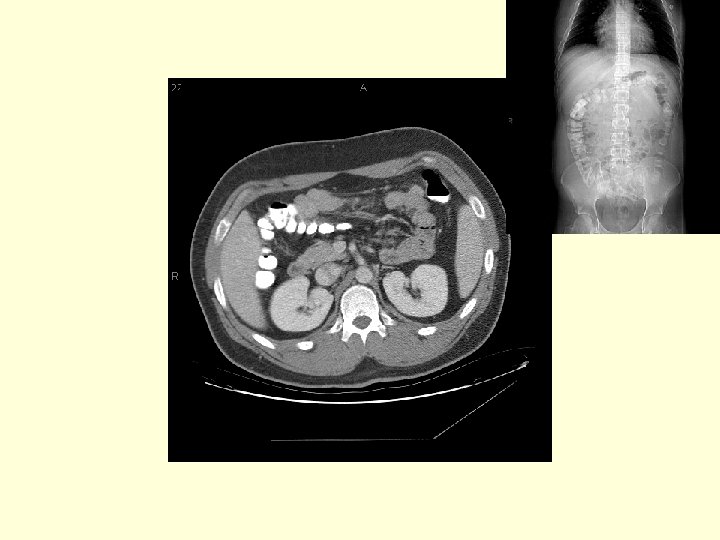

What is this venous structure extending from the left kidney to the IVC? This is the left renal vein

What is this vessel coming of the aorta? Hint, it is colonic supply and below the level of the SMA. Inferior mesenteric artery